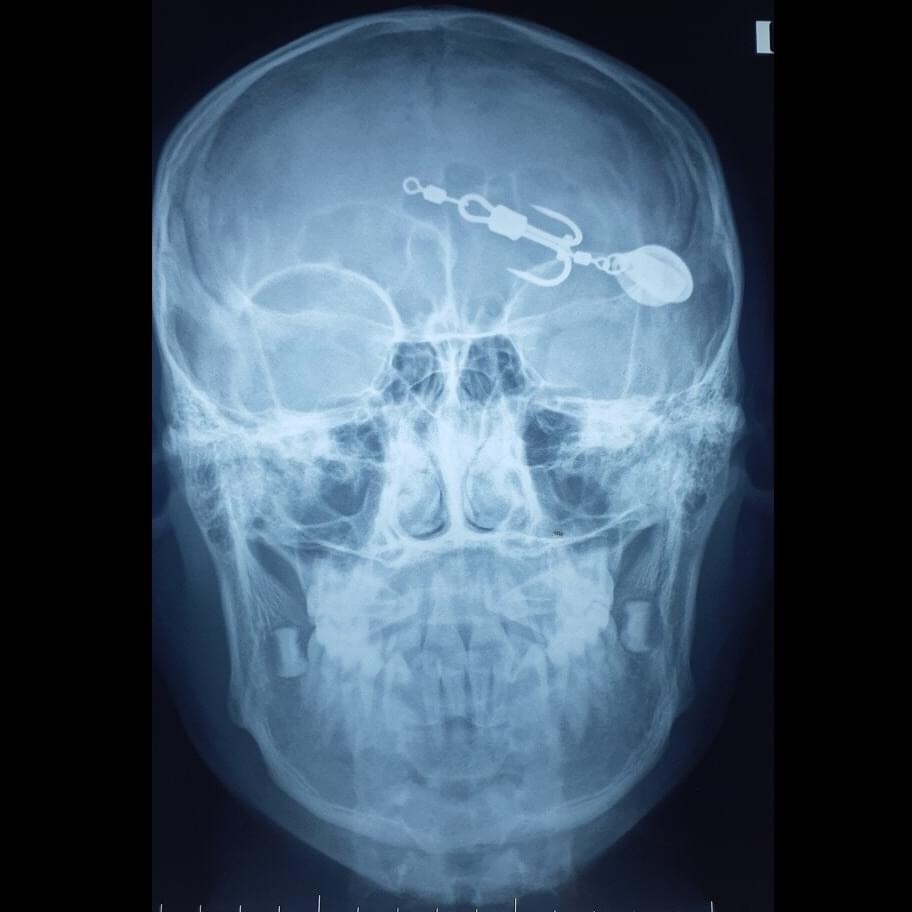

Hình chụp X-quang đầu bệnh nhi. Ảnh: BVCC.

Bệnh nhi V.T. (13 tuổi, trú tại huyện Tam Nông, Phú Thọ) được đưa đến cấp cứu tại Trung tâm Y tế huyện Thanh Sơn trong tình trạng tỉnh táo, mặt bị dị vật găm sâu, vết thương không chảy máu nhiều.

Dị vật là một chiếc móc câu 2 lưỡi đâm thấu mi trên vào trong ổ mắt trái, có nguy cơ làm tổn thương nhãn cầu.

Tại khoa Ngoại tổng hợp, qua thăm khám và làm xét nghiệm cận lâm sàng, bệnh nhi được bác sĩ chẩn đoán dị vật hốc mắt trái và chỉ định phẫu thuật lấy dị vật hốc mắt.